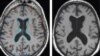

B Vitamini Hafızaya İyi Geliyor